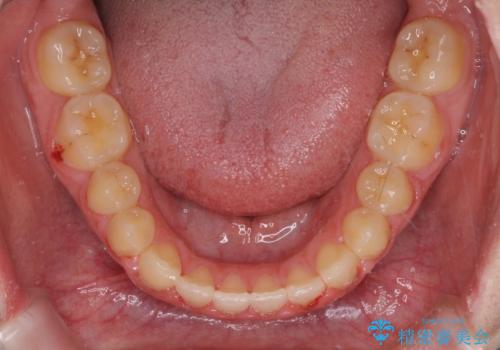

上顎骨を拡大したことで、下顎の歯列を上顎が受け入れられるようになりましたが、インビザラインでは咬み合わせを改善させることができなかったため、ワイヤー矯正にて仕上げることとしました。

ワイヤーを使用したものの、上下前歯のオープンバイトがなかなか改善されませんでしたが、患者希望により治療終了となりました。